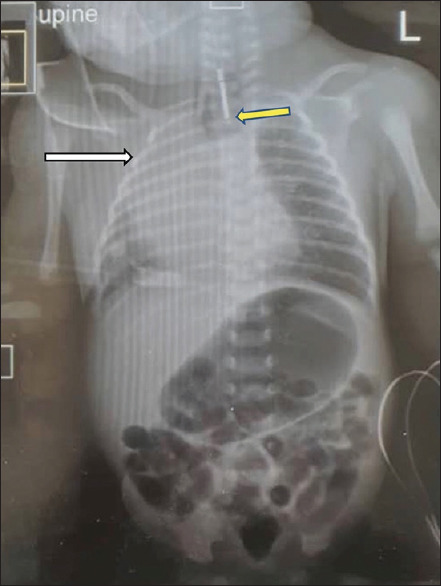

摘要:在尼日利亚和西非次区域,食道闭锁伴气管食道瘘(TOF)的治疗对儿科医生来说无疑是一项非常艰巨的任务,这并不一定是由于缺乏技能,而是由于对新生儿重症监护的巨大需求,而在我们这个地区,重症监护往往缺乏成功所需的基础设施。此外,开胸手术的使用也增加了对新生儿重症监护的需求,导致大量新生儿病情严重,死亡率高。因此,在我们这个次区域,要赶上发达国家对这种复杂病症管理的发展趋势,仍然进展缓慢。自2000年首次成功记录胸腔镜修复伴有TOF的OA后,该技术不断发展和完善,胸腔镜修复术已迅速成为修复所有类型OA(包括长间隙异常)的黄金标准。本文报告了我们在西非次区域首次对两例伴有TOF的OA进行胸腔镜修复的经验。

Abstract: Management of oesophageal atresia (OA) with tracheoesophageal fistula (TOF) in Nigeria and the West African subregion has no doubt been a very demanding task for paediatric surgeons, not necessarily due to lack of skills, but due to the significant demand on neonatal intensive care, which in our region, is often fitted with the poor infrastructure needed to make this a success. Furthermore, the use of open thoracotomy has increased this demand resulting in a significant number having severe morbidities and significant mortality rates. Hence, in our subregion, there is still a slow progression to meet up with the evolving trend of the management of this complex condition in the developed world. Following the first documented successful thoracoscopic repair of OA with TOF since 2000, there has been a progressive evolution and refinement of this technique, such that thoracoscopic repair is fast becoming the gold standard for the repair of all types of OAs, including long-gap anomalies. This article reports our experience with the first two cases of thoracoscopic repair of OA with TOF in the West African subregion.